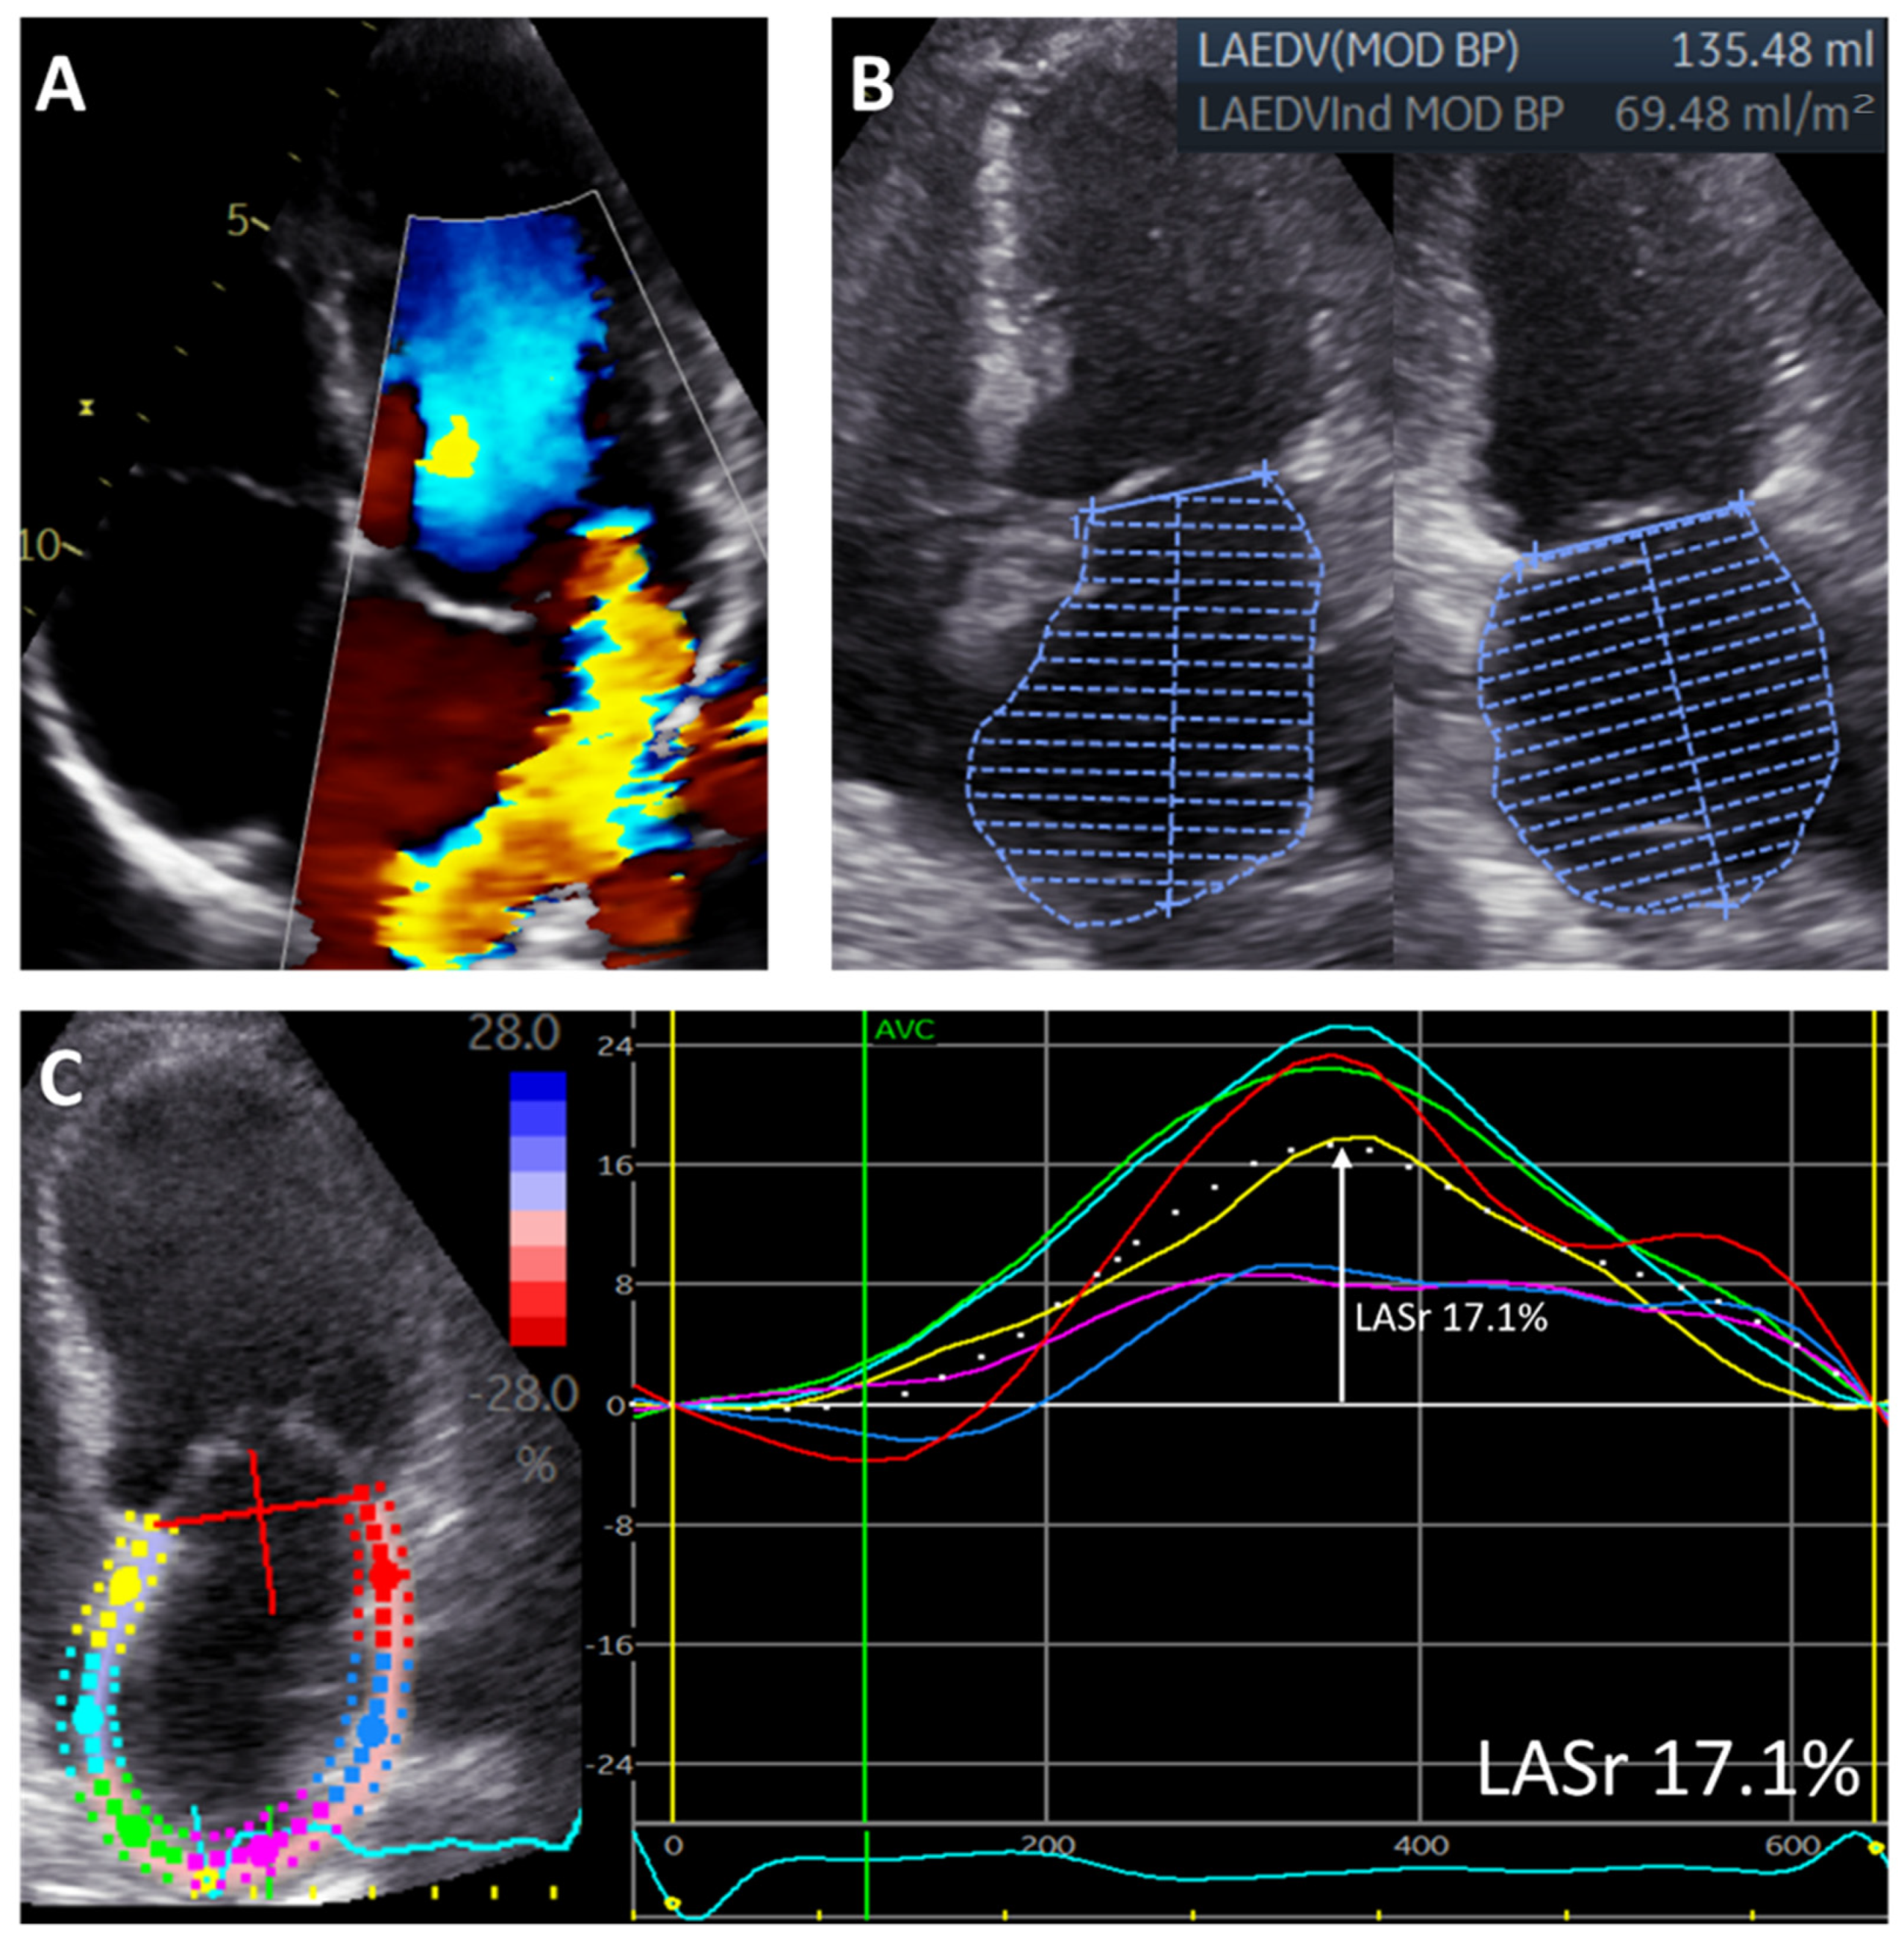

| LAVi, mL/m2 | 56 ± 28 |

| LASr, % | 23.6 ± 9.4 |

| LAVi, mL/m2 | 56 ± 28 | 32 ± 17 | <0.001 |

| LASr, % | 23.6 ± 9.4 | 17.3 ± 7.5 | <0.001 |